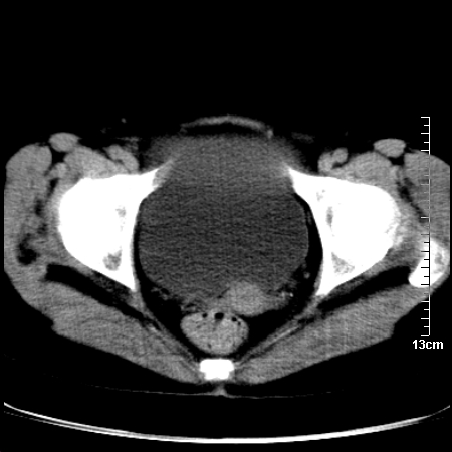

术前的疏忽,手术前诊断阑尾炎,但是没有常规做b超,导致术后1周检查发现 1。实性包块?2。腹腔术后脓肿?

病史:病人一周前诊断阑尾炎,未做b超,手术发现阑尾化脓,(没有留意有无包块),术后1周病人发热,血象:1.6万,做b超发现,随ct检查,上传图片

巨大囊实性包块,边界大部尚清楚,不太像脓肿的表现。应该做个增强检查除外盆腔肿瘤。

脓肿可能性大. 因回盲部区域化脓性兰尾切除残端感染改变征像与实性肿块关系密切.肿块上界至右下腹,下界至盆腔膀胱上缘, 如果是实性肿块在兰尾术中可能就会发现. 所以术后一周病人高烧, 白细胞增高,临床表现支持脓肿.

盆腔一边界大部份清晰囊实性肿块,其周腹脂未见确切异常,其一端与右侧附件相连。考虑右侧附件肿瘤。

如果能进行肠道准备就好了!盆腔内巨大囊实性包块,右前缘与周围肠管分界不清,病灶内前部的气体是否为肠管内气体形成的假象不能确定。

这么大一包快手术当中没有发现?值得怀疑!结合化脓性阑尾炎病史,首先考虑脓肿!不排外附件来源的肿瘤,建议增强扫描!!

因术前未做相关检查,故漏诊完全有可能!若脓肿这么大,临床不会单纯是阑尾炎的体征!支持:盆腔肿瘤——首选:附件来源的肿瘤,建议增强扫描!!!

我在为一名女高中生做阑尾炎术前b超常规检查时发现右侧附件区囊性占位,其中可见脂类回声,遂诊断畸胎瘤,后经妇科及外科联合手术证实,该病例不是与我的那例巧合吧.